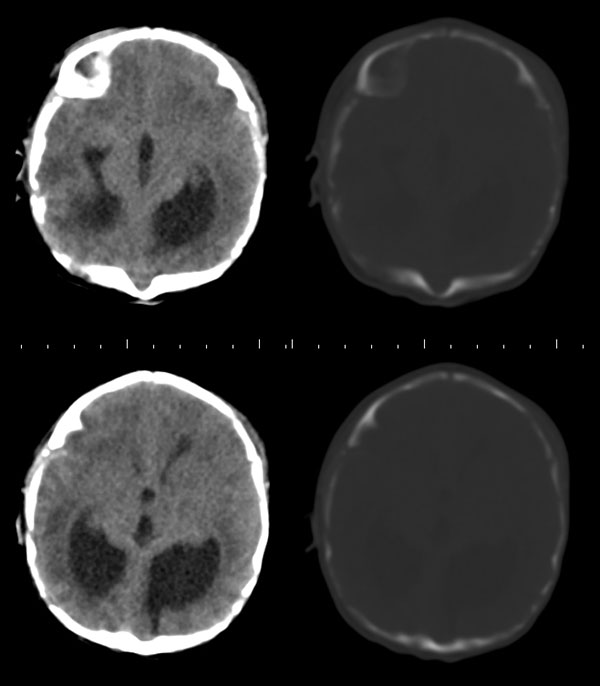

枕骨缺损,脑膜脑膨出。同时第4脑室挤压变形、闭塞,致使第3脑室、双侧侧脑室显著积水、扩张,过高的颅内压推挤脑实质,致使颅骨内板出现多而且深的脑回样压迹,脑细胞水肿,皮质、白质分界不清。

颅骨内面凹陷——过高的颅内压推挤脑实质,过高的颅内压推挤脑实质,致使颅骨内板出现多而且深的脑回样压迹

1枕骨脑裂畸形

2典型脑膜脑膨出

3脑积水

脑膜膨出没有问题,但是颅骨怎么长成这样,还是第一次看到;